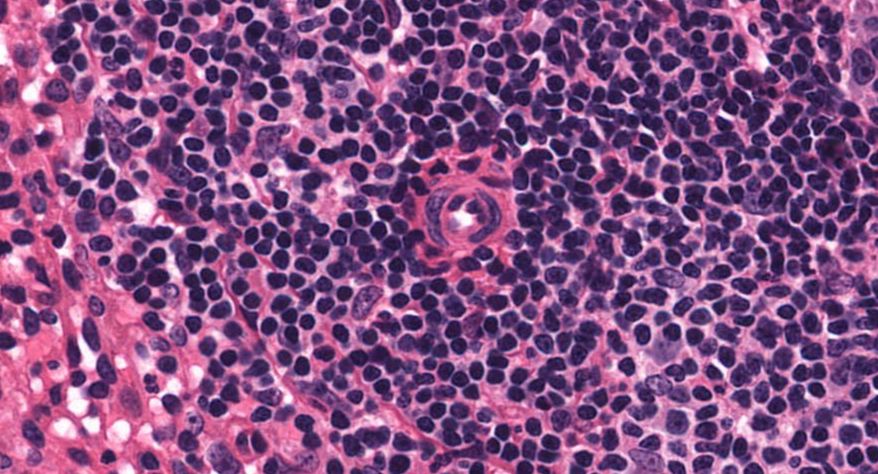

低倍镜:胸腺表面包有薄层结缔组织构成的被膜,结缔组织深入实质,将胸腺分成许多不完整的小叶。每个小叶分为周围的皮质和中央的髓质两部分。皮质中胸腺细胞排列密集,故染色深;髓质中胸腺细胞较少,胸腺上皮细胞多,故染色浅,其中可见染成红色的圆形小体-胸腺小体。高倍镜:胸腺小体大小不等,由几层至十几层扁平的胸腺上皮细胞呈同心圆状排列而成,其外周的细胞较幼稚,细胞核明显;小体中央部分的上皮细胞已退化,细胞核消失,胞质呈均质状,染成红色。

7.胸腺小体1